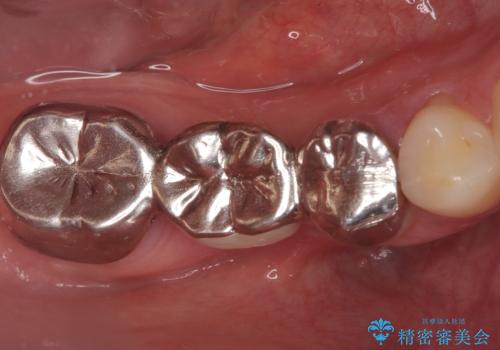

右下奥歯の5・6・7番に装着されていたブリッジの不具合を主訴にご来院されました。ブリッジは汚れが溜まりやすく、土台となる歯への負担も大きいため、今回は「それぞれの歯を独立させて、自分の歯を長持ちさせたい」というご希望に合わせ、以下の計画を立案しました。

ブリッジを外し、欠損している6番にインプラントを埋入。